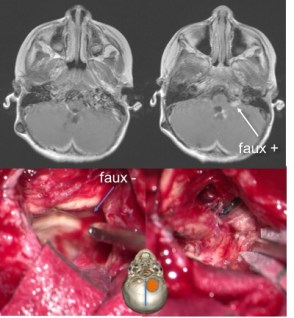

en cas d’exérèse incomplète, une réintervention de second-look peut être indiquée ; l’interprétation de l’IRM postopératoire est cependant souvent difficile avec risque de faux positif et de faux négatif (cf. ci-dessus).